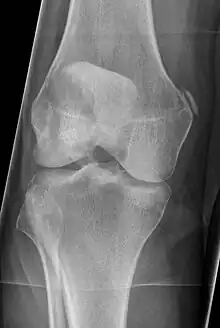

Diagnosis is typically made on radiographs demonstrating the Pellegrini-Stieda syndrome sign accompanied by pain or restriction of range-of-motion of the knee joint.[2] Pellegrini-Stieda syndrome sign is typically described by a longitudinally linear opacity, which is a process that is describes characteristic of calcification in the soft tissue located medial to the medial femoral condyle.[2] This calcification seen on imaging represents the ossification of the medial collateral ligament, which typically does not develop until approximately three weeks after the initial injury.[2]It is important to note to distinguish this radiographic finding from that of a medial femoral condyle avulsion fracture, which is an injury in which a pulling force of a tendon or ligament fractures away a piece of the bone from its attachment site.[2]